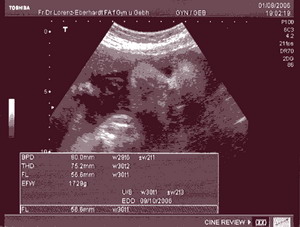

Voltam ultrahangon azt hittem irtam róla.Most is mondta a dokim hogy nagy baba lesz éshogy nagyon valoszinü hogy elöbb meglesz.A halántékcsontjai között a távolság 8cm a combcsonthosza meg 6cm.És már megfordult.Pedig azt mondták hogy azt biztos észre fogom majd venni merrt az nagyon intenziv mozgás.Nekem még sem tünt fel.Én kinek szóljak ha majd eljön az idö????

Beuci21, tényleg jó nagy babád lesz!! :) Ezek a méretek!